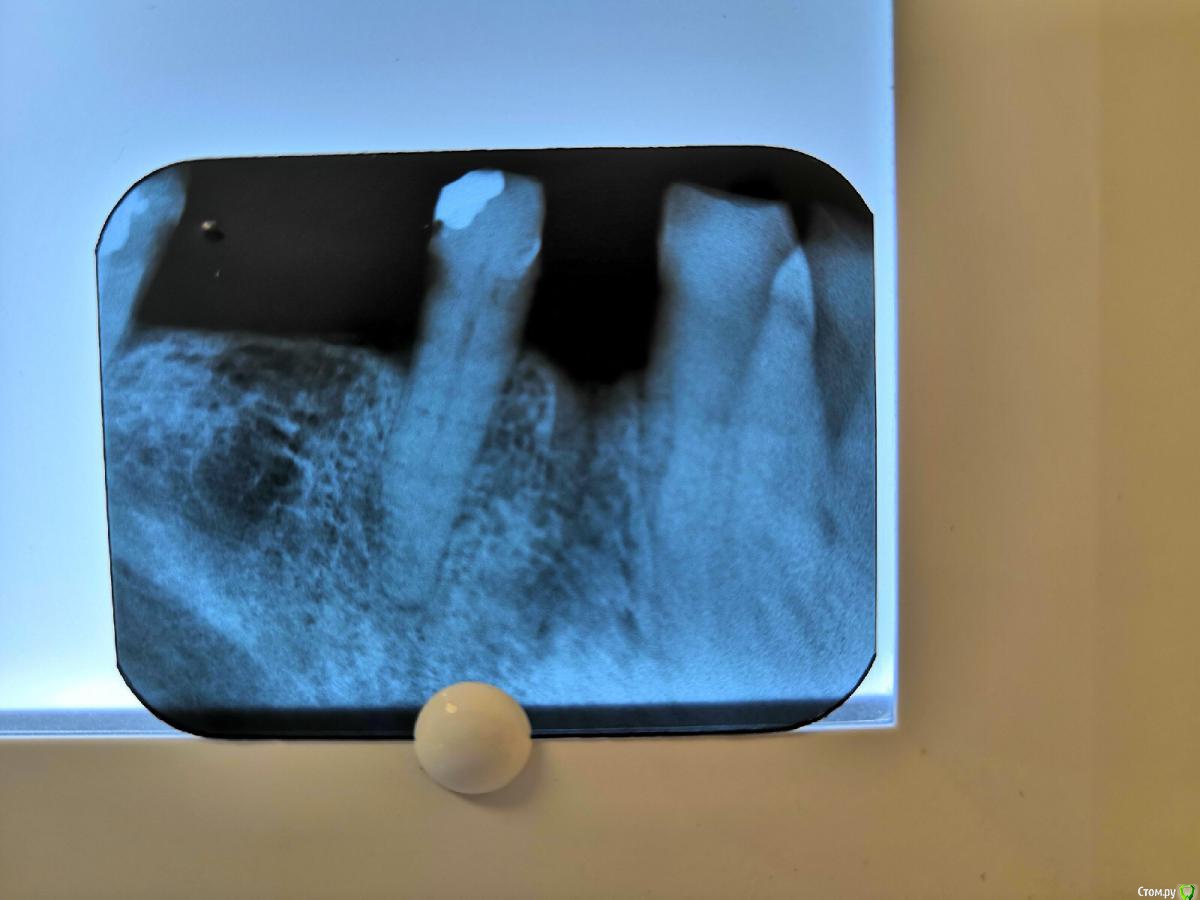

Здравствуйте не могли бы подсказать сколько вы видите каналов в зубе 2.7.Мне кажется там 2 корня(2 канала)нашёл медиально—щёчные канал и небный(расширил на периапикальный снимке Гейтсом ) дистально щёчный никак не смог найти,хотя устья других каналов были приличные(сразу обозримые и зондируемые).На другом снимке зуб 45 ,протяженность канала обрывается на границе средней и апикальный трети ,думаю там бифуркация 4аналов? или мне кажетсяpost-55917-0-65872500-1562703527_thumb.jpegpost-55917-0-21792800-1562703539_thumb.jpegpost-55917-0-24560700-1562703559_thumb.jpeg

Сделайте снимок с инструментами, не поможет - отправьте на клкт. В целом, зуб похож на обычный, т.е. 3-4 канала. 45, имхо, двухканальный, но это не точно.